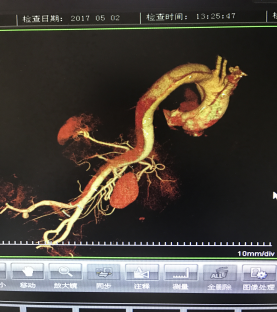

5月2號劉大伯照常早起干活,突然胸部劇烈疼痛,難以忍受,全身大汗,同時伴有右上肢發(fā)涼,他心想這次心絞痛比之前嚴重的多啊,趕緊叫上孩子到吉林國文醫(yī)院心血管內(nèi)科住院,患者長期高血壓病史,血壓一直控制不理想,大夫給他做了檢查,測左上肢血壓:82/45mmHg,右上肢血壓測不出,心率52次/分,右側(cè)肱動脈、尺動脈、橈動脈搏動消失,左側(cè)股動脈搏動較右側(cè)弱?!霸懔耍p側(cè)血壓差別這么大,是不是主動脈夾層了?”,接診大夫趕緊找來李主任,李主任反復(fù)詢問患者病情,表情突然凝重起來,患者胸痛這么明顯,血壓低的厲害,主動脈夾層的可能性很大。二話不說,李主任立即聯(lián)系影像科的醫(yī)生準備做主動脈CTA,移動患者做檢查的過程大夫們非常小心,嚴密監(jiān)測患者血壓變化情況。兩個小時后結(jié)果出來了,主動脈夾層從升主動脈一直撕裂到左側(cè)髂總動脈?。?!

從開始學醫(yī)到現(xiàn)在已經(jīng)快9年了,主動脈夾層患者也見過一些,但像劉大伯這種危險類型的還是第一次見到,心里真的為他捏把汗,撕裂的主動脈隨時都有可能破裂,生命隨時可能終止,要知道主動脈夾層的死亡率非常的高,約50%的患者發(fā)病后48小時死亡,約90%的患者發(fā)病1個月內(nèi)死亡。

李主任詳細的與劉大伯的女兒交代了病情,手術(shù)是挽救生命的唯一辦法,為了劉大伯的一線生機,我們積極聯(lián)系了我省權(quán)威的心血管外科,并做了詳細的匯報,兩家醫(yī)院對此非常重視,為劉大伯開通了綠色通道,安全的把他總到上級醫(yī)院,當天便給他進行血管置換及覆膜支架植術(shù)。他術(shù)后恢復(fù)的很好,后來劉大伯的女兒看望我們,感嘆道:沒想到國文醫(yī)院心內(nèi)科應(yīng)急能力這么高,在那么短的時間內(nèi)診斷明確,才給了我的老父親手術(shù)的機會。